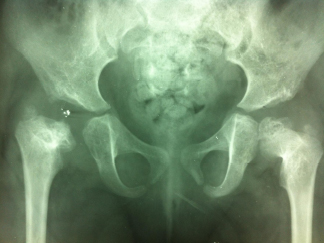

Une longue histoire de hanches

Mme D. est née le 01/01/1945.

La première radiographie des hanches est le 29/11/1946.

Puis le 20/07/1948.

Puis le 20/07/1949.

Puis le 17/03/1955 elle a 10 ans :